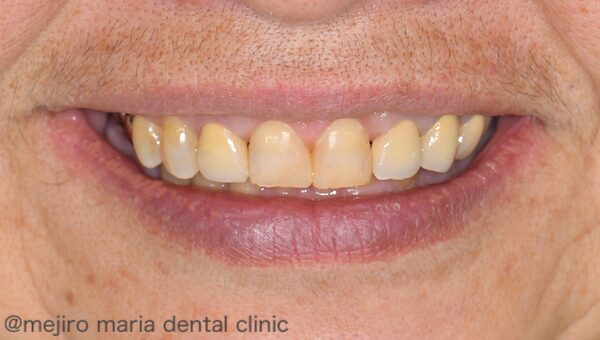

術直後の腫れや疼痛はほとんどなく、術後約1週間で抜糸を行いました。術後の歯肉のラインは、時間をかけながらゆっくりと変化していきます。今回の患者様は、もともと歯冠補綴が必要な部位があったので、約半年間と十分な治癒期間を待ち、補綴治療へと移行しました。

最終的なスマイル時の写真では、歯のサイズが適正になり、歯肉の露出量も改善され、審美的に良い治療結果を得ることができました。